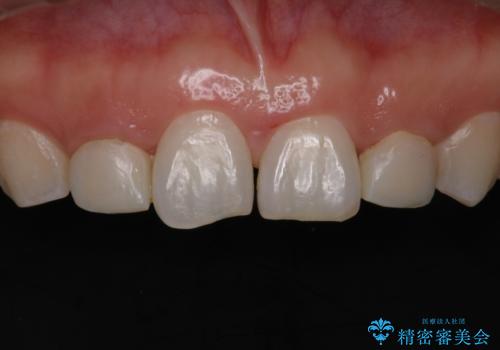

歯の形気になる!! セラミック治療 前歯( エクセレント)

- 歯の形が気になるということで以前入っていたプラスチックのものから、セラミックでの治療を希望されたので行いました。

色や形をこだわりたいということで、当院最上位ランクのエクセレントにて治療を行いました。

当院で患者様の口腔内の写真を撮影し技工士さんに指示を出して完成します。

患者様はかなり喜ばれておりました。